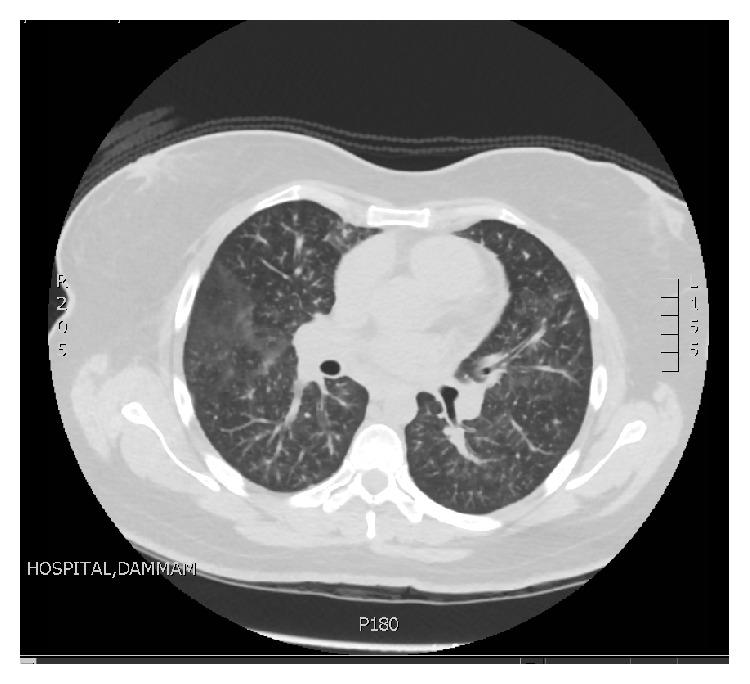

年轻女性不明原发恶性肿瘤的致命性肺肿瘤栓塞性微血管病

Fatal Pulmonary Tumor Embolic Microangiopathy in Young Lady without Known Primary Malignancy.

Pulmonary embolism (PE) is a common cause of morbidity and mortality in hospitalized patients. Malignancy, prolonged recumbence, and chemotherapy are renowned risk factors for development of clinically significant PE. Cancer exerts a multitude of pathophysiological processes, for example, hypercoagulability and abnormal vessels with sluggish circulation that can lead to PE. One of the peculiar characteristics of tumor cells is their ability to reach the circulation and behave as blood clot-not a metastasis-occluding the pulmonary circulation. We present a case of fatal pulmonary embolism diagnosed histologically to be due to tumor cell embolism.

摘要

肺栓塞(PE)是住院患者发病和死亡的常见原因。恶性肿瘤、长期卧床和化疗是临床上显著PE发生的著名危险因素。癌症会引发多种病理生理过程,例如高凝状态和血管异常伴循环缓慢,进而可能导致PE。肿瘤细胞的一个独特特征是它们能够进入循环系统并表现为血凝块——而非转移灶——阻塞肺循环。我们报告一例经组织学诊断为肿瘤细胞栓塞导致的致命性肺栓塞病例。